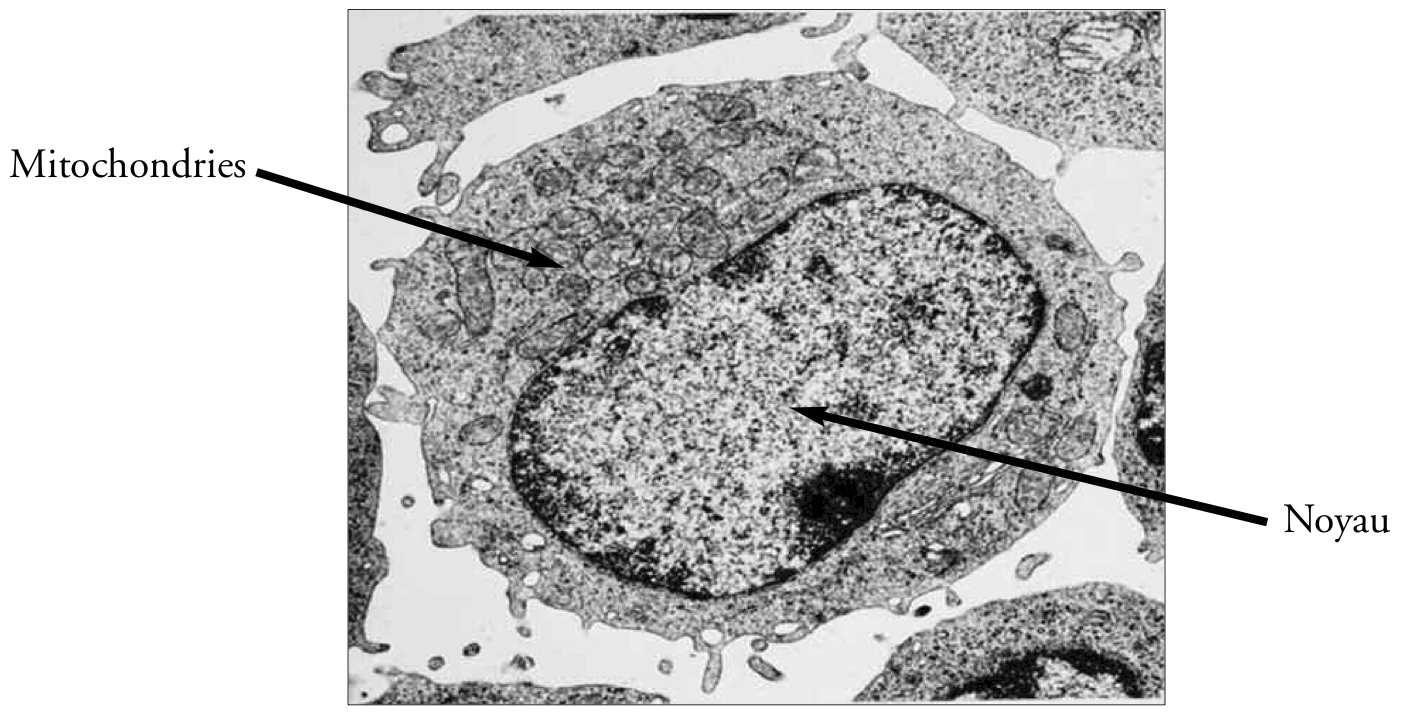

La molécule d’ADN est située à l’intérieur de chaque cellule de notre corps humain. Toutes les cellules d’une personne possèdent le même ADN.

Photographie n° 1 - Cellule en microscopie électronique